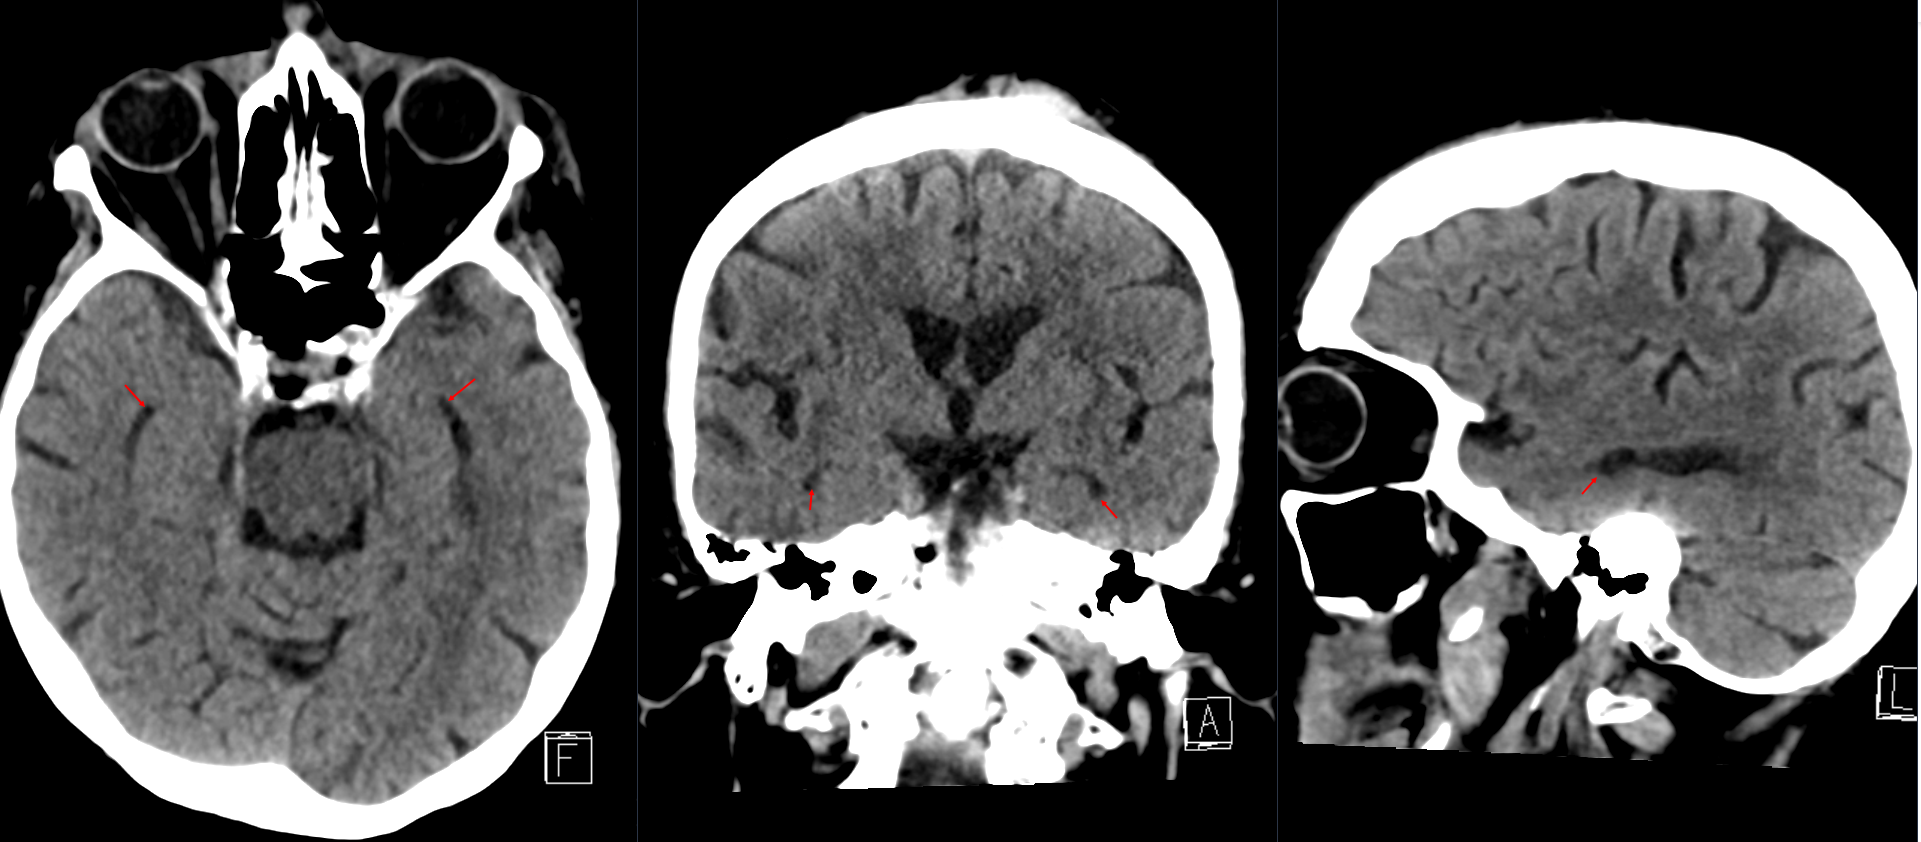

Das Temporalhorn des Seitenventrikels ist üblicherweise in einem CT oder MRI nicht sichtbar. Ein sichtbares Temporalhorn kann ein Zeichen für einen beginnenden Liquoraufstau sein.

Temporalhorn des Seitenventrikel im CT

Darstellung des Temporalhorns des Seitenventrikels in verschiedenen Ebenen in einer CT Bildgebung.